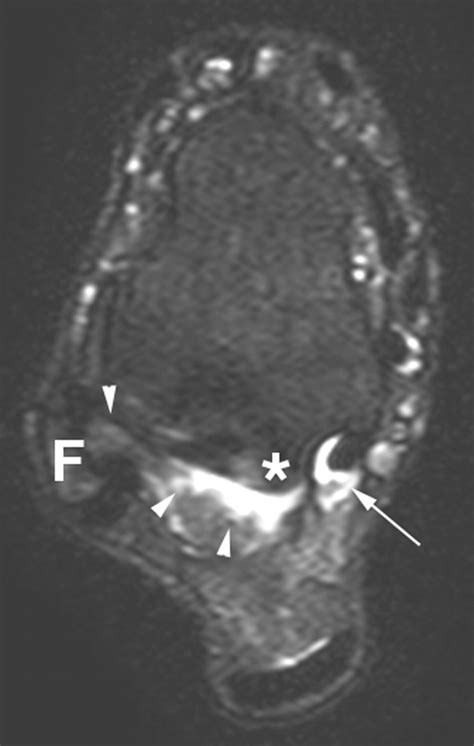

Imaging tests, such as X-rays, MRI, or CT scans, can provide detailed images of the ankle joint and surrounding structures. These tests can help identify any abnormalities, such as bone spurs, fractures, or soft tissue damage, that may be contributing to the symptoms.

• posterior ankle impingement mri